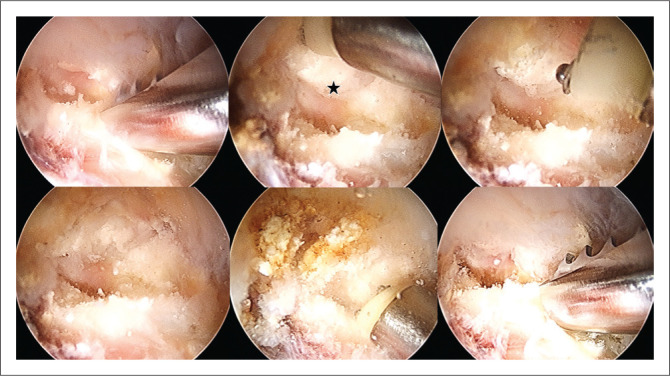

This report describes a rare case in which double calcifications of the acetabular labrum and rectus femoris occurred concomitantly in a middle-aged female patient who was treated successfully with surgical intervention via hip arthroscopy.

Contribution: This case highlights the existence of various types of calcifications around the acetabulum, with a proposed new classification system for acetabular and periacetabular rim ossifications.